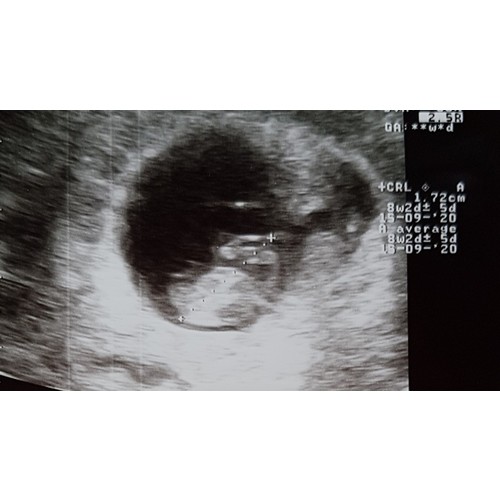

8 weken 2 dagen inwendige echo